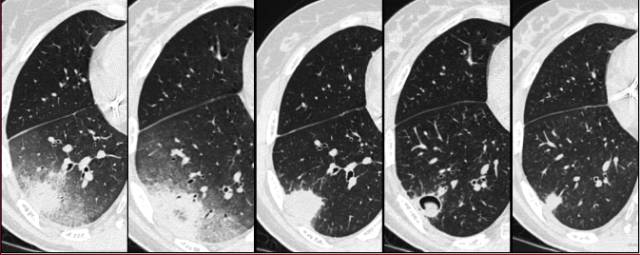

图3 骨髓移植患者双侧肺结节和实变,伴GGO。右图显示治疗后吸收良好。血管侵袭性曲霉病

恢复期(开始治疗后的2~3周,诊断早期意义不大)常见的另一个影像征象是空气新月征,来自于毗邻肺实质坏死肺碎片分离。

图4 曲霉病治疗后,肺内病灶的自然进程。第4张图可见空气新月征